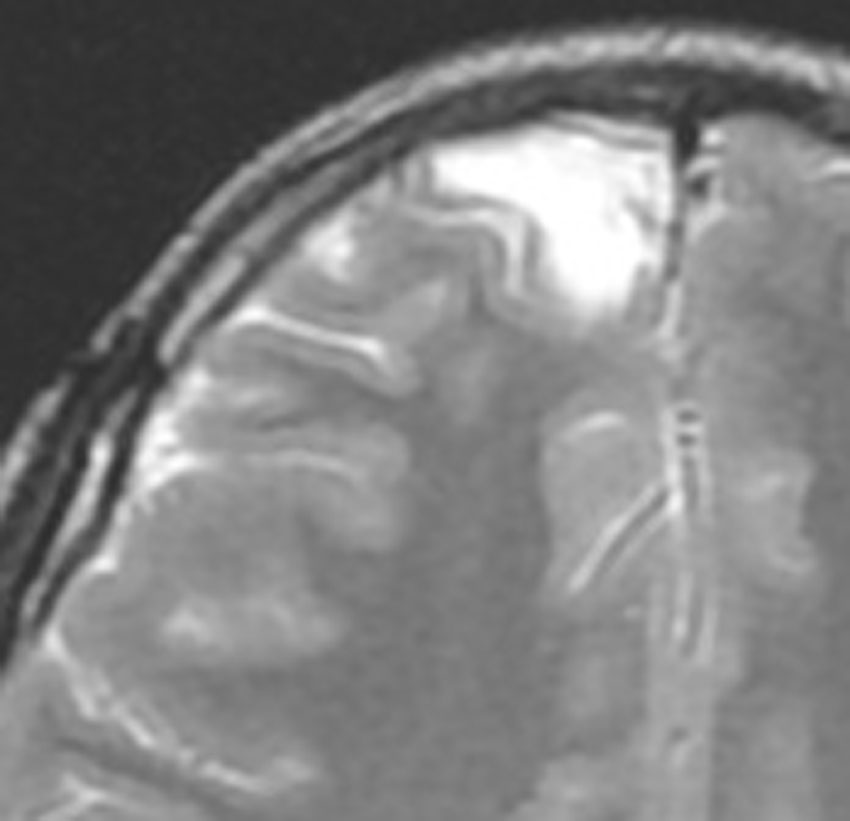

画像診断

- とても難しいといえます,特徴的な所見がないからです

- ほとんどが髄膜に接する脳表を巻き込む病変なのです

- T1強調では等信号から低信号

- T2強調画像では低信号領域と血管のflow-voidがみられます

- ガドリニウム増強では不規則な増強像を見ることが多いです

- T2低信号の部分(結節)が強くガドリニウム増強されることも特徴かもしれません

難治性てんかんで発症した小児ですが,どう見てもDNTなのかなと思います。石灰化もありません。一般的に,meningioangiomatosisの術前診断は困難であると言えます。いずれにしても治療はlesionectomyです。